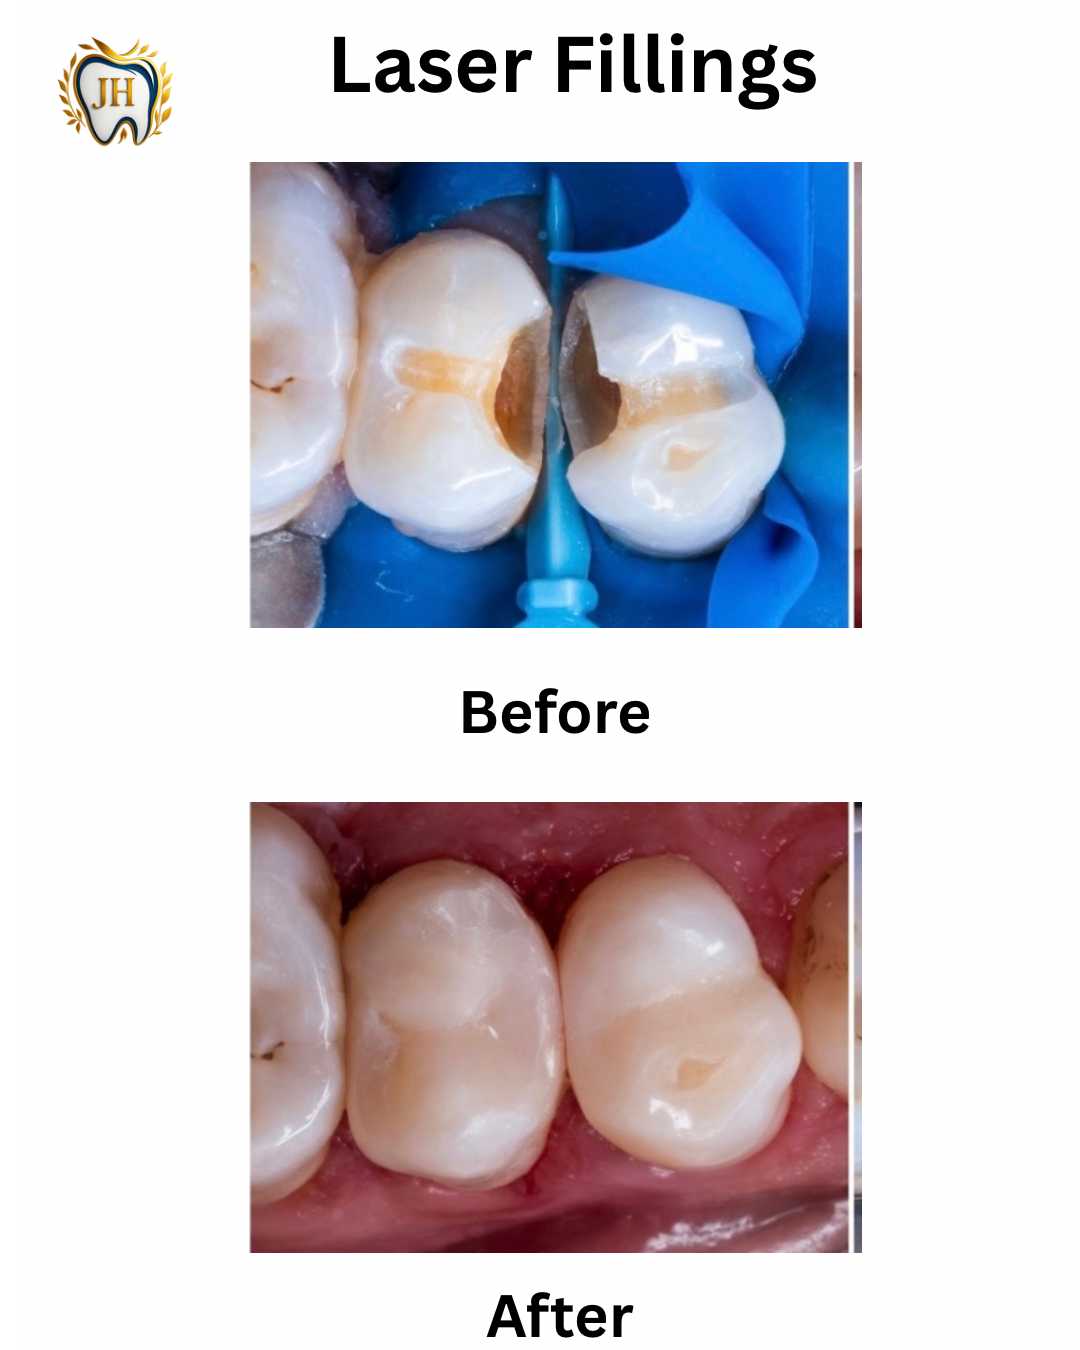

- Composite Fillings

- Transformations